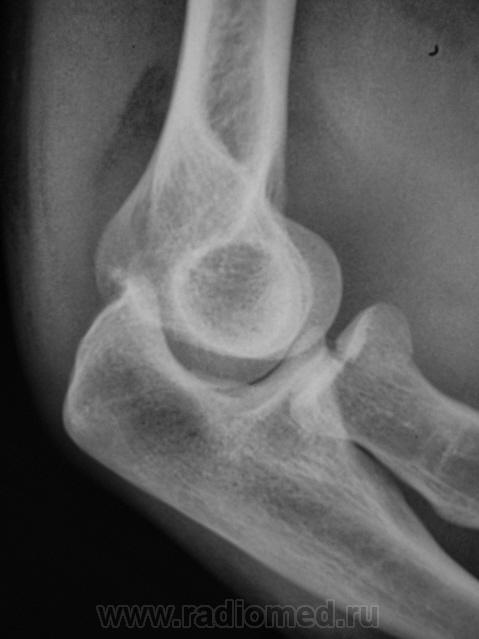

Рентгенограмма в прямой проекции.

Предположу продольный перелом головки луча с допустимым смещением.